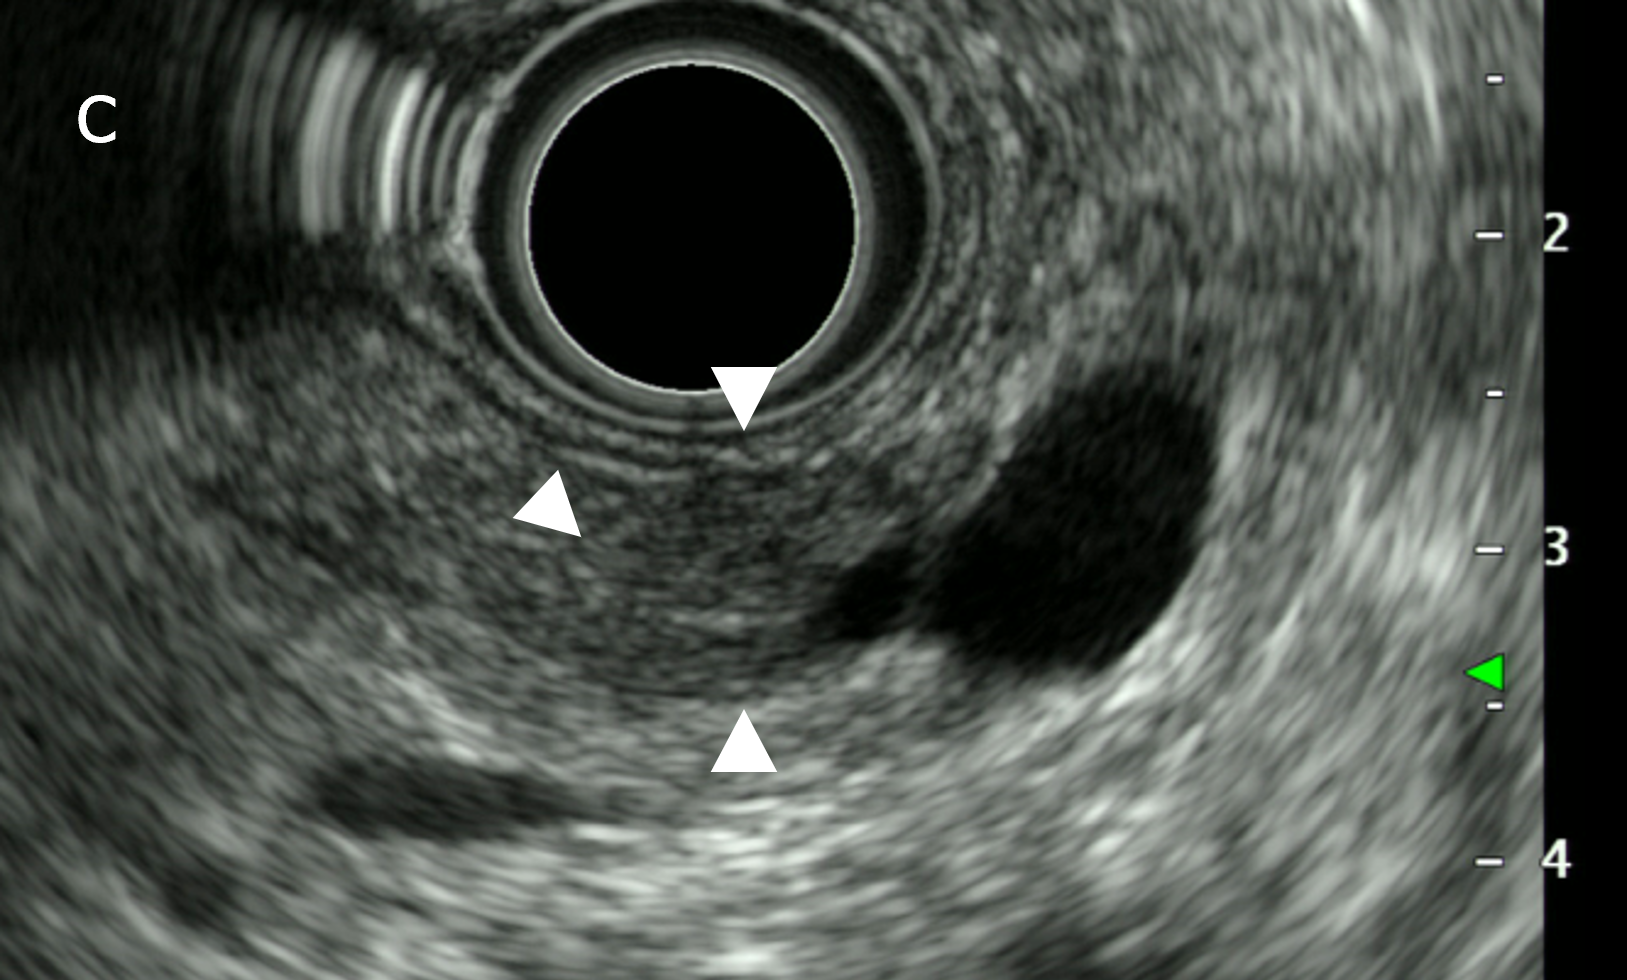

図3(a):CT(a)では、白矢印の部分に膵の萎縮を認める。

図3(b):MRI(MRCP)(b)では膵尾部の主膵管が白矢印の部位から拡張している。

図3(c):EUS(c)では、主膵管の拡張がはじまる部位の周囲に淡い低エコー領域(白矢印)を認める。以上から、強く早期の膵癌を疑い、複数回の膵液細胞診を行い腺癌と診断、手術ののち膵上皮内癌と最終診断された。